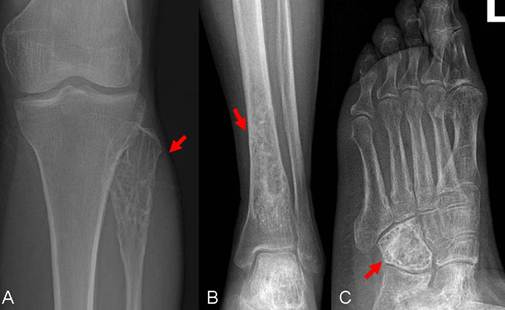

Figure 1

X-rays (anterior view) of the left tibia and foot show osteolytic lesion causing irregular cortical bone in the cuboid bone, distal tibia and fibular head with a surrounding slight soft tissue swelling (arrow).

A 59-year-old female patient visited our orthopaedics clinic with complaints of increasing swelling, pain, anesthesia of the left lateral lower leg and extension loss of the left great toe of six months duration. On physical examination a 2.0 cm mass showing tender and palpable was located on the posterolateral aspect of the proximal lower leg, appearing to arise from the left fibular head. A positive Tinel sign at the proximal fibula led us to suspect compressive neuropathy of the peroneal nerve. Radiographs showed a lytic lesion causing irregular cortical bone thinning in the body of the upper fibula with a surrounding slight soft tissue swelling (Figure 1 A). Then we made further both lower extremities X-ray examination, found the similar osteolytic lesion in the distal tibia and cuboid bone (Figure 1 B,C). Routine blood laboratory data were within normal limits at the time and the patient had no previous history of tumor and family history of tumor. However, magnetic resonance image (MRI) for left lower extremity manifested multiple solid lesions in the gastrocnemius muscle at the level of the head of the fibula and multifocal lesion with irregular borders at the upper fibula, distal tibia, cuboid bone and calcaneus (Figure 2). Right lower extremity and other parts of the left lower extremity were apparently normal. The chest radiograph was normal. Histopathological examination of the needle aspiration biopsies from cuboid bone and tibia showed a neoplastic infiltration composed of vascular structures of different caliber lined with mild atypical endothelial cells in a myxoid stroma. The epithelioid cytomorphology were polygonal or spindle shaped, which had vesicular nuclei, unapparent nucleoli and eosinophilic cytoplasm with intractyloplasmic vacuoles and were easily identified (Figure 3). Immunohistochemical study showed immunoreactivity for SMA, CD31, CD34, CD68 and vimentin. No immunoreaction was observed for epithelial membrane antigen (EMA). Owing to these findings; there was not much doubt that the patient was diagnosed as multifocal epithelioid hemangioendothelioma.